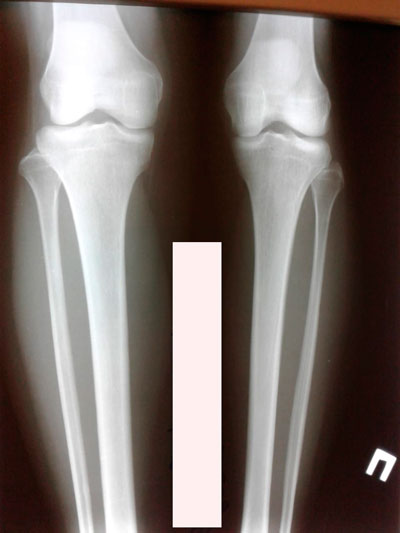

Исходник - 24 года.

Диагноз: врождённое укорочение правой голени на 4 см.

Костный регенерат в динамике, в процессе удлинения.